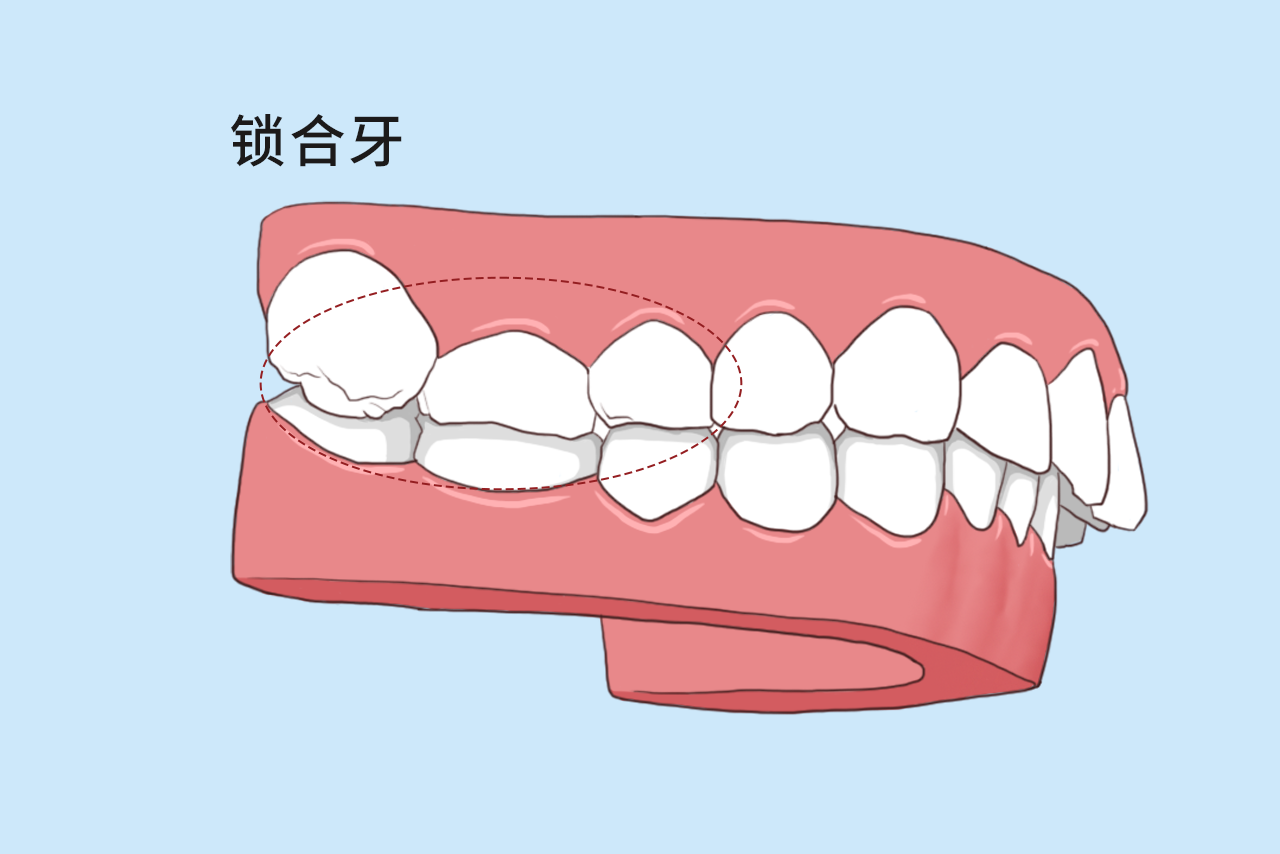

锁牙合

你的牙没缺没烂就是嚼不动有可能是后牙锁合在搞事情

锁牙合

锁合牙图片